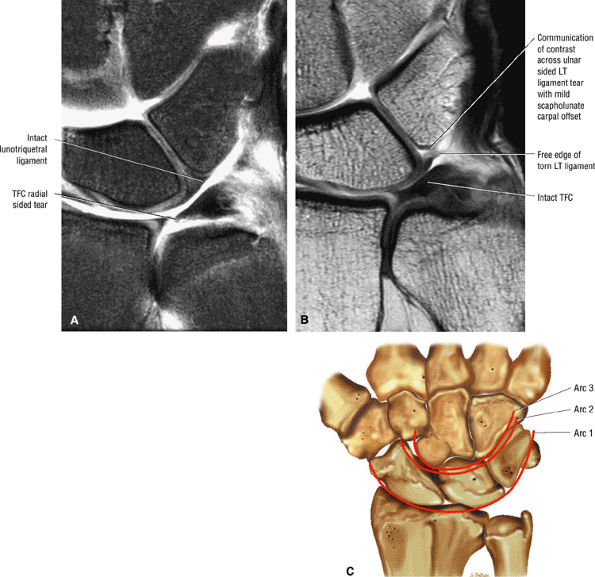

FIGURE 10.35 LUNOTRIQUETRAL LIGAMENT.